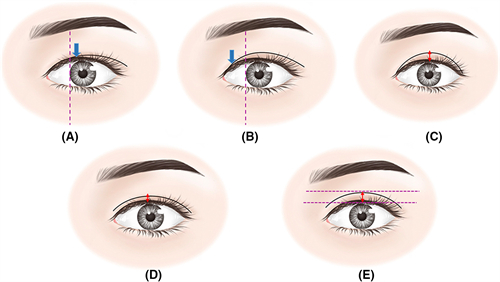

眼部修复特色运用显微血管吻合技术处理瘢痕组织,通过"眶隔脂肪动态复位术"解决传统修复术后僵硬问题,二次修复成功概率保持91.4%的行业高位。

典型病例2:双眼皮修复实例,原切口粘连性凹陷经脂肪微粒移植联合重睑重建,术后睁眼弧度自然度达9.2分(10分制),瘢痕增生率控制在3%以下。